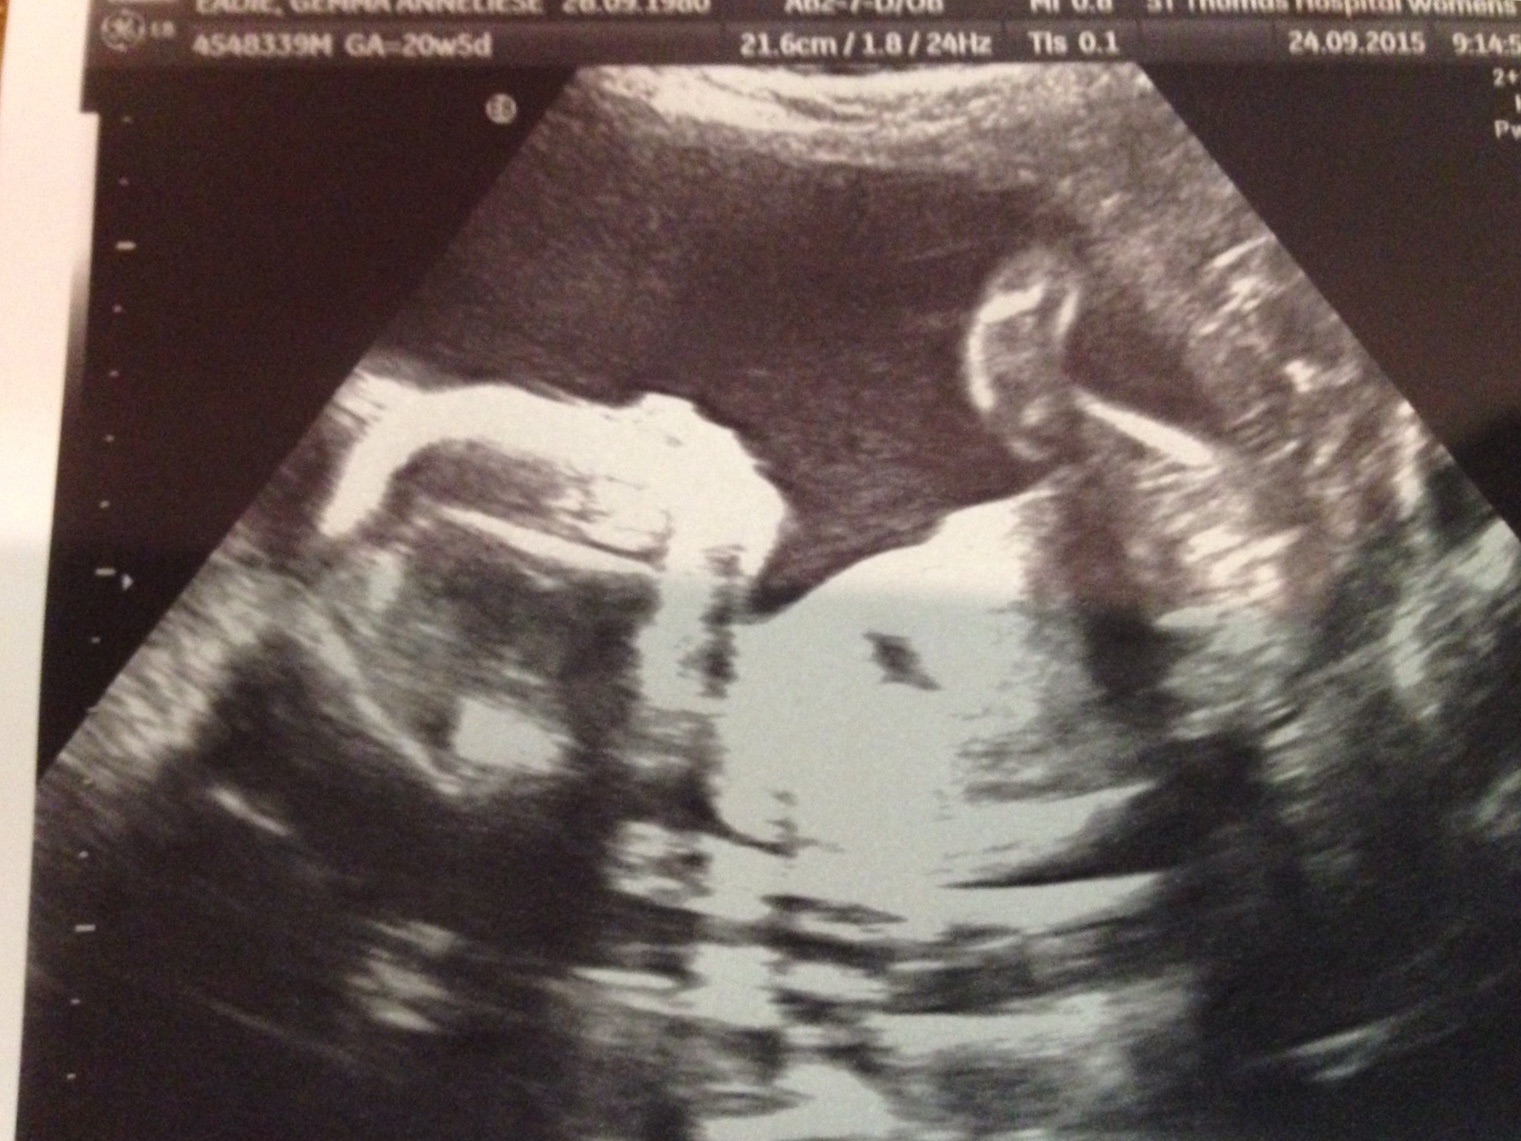

Hello ladies, just wondered what your thoughts were on this scan. I can see some lines in the nub region... They look fairly straight, but not sure if this means girl? Any thoughts?

At 20 weeks you need a potty shot.